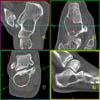

Foot Pathology: Tumors

Diagnosis:

Unicamerel bone cyst of the calcaneus.

Chondroblastoma.